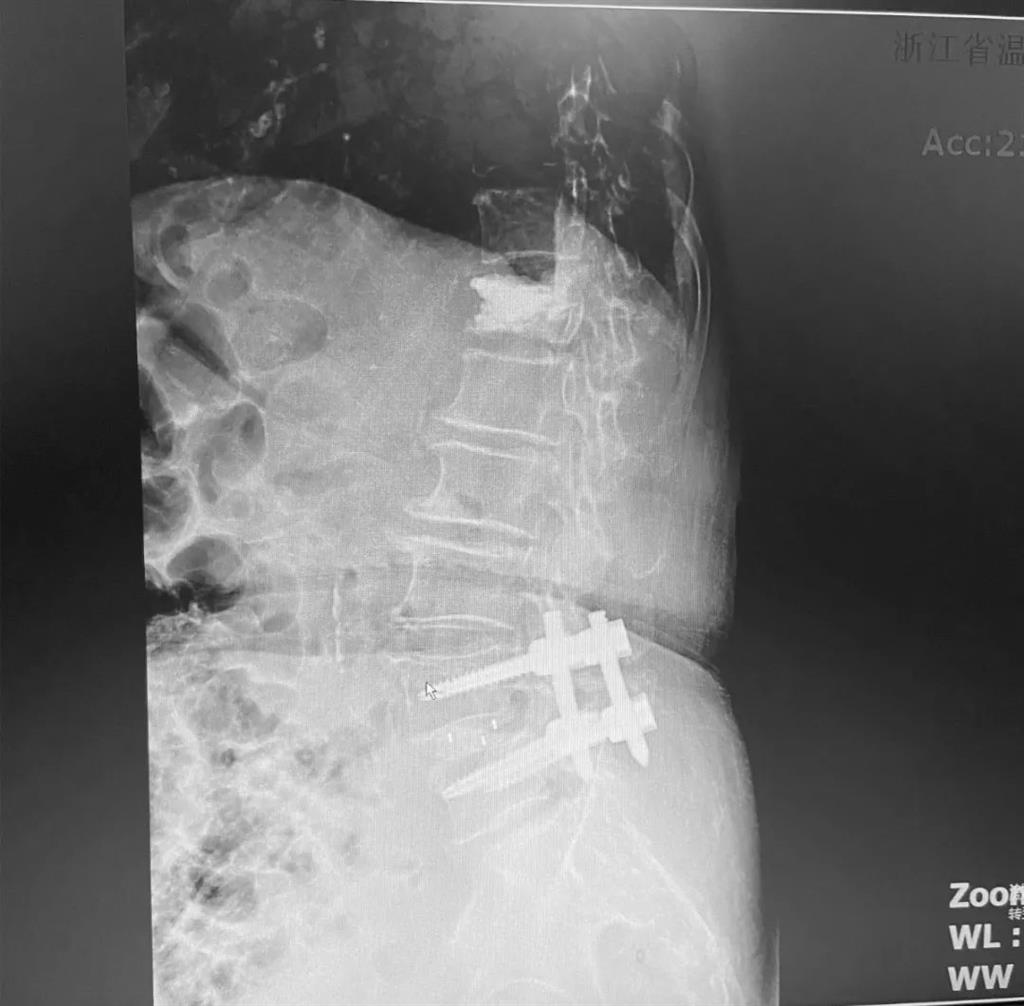

據(jù)了解,脊柱內(nèi)鏡下腰椎融合術(shù)只需要打幾個(gè)“鑰匙孔”即可完成。聽起來是不是很簡單?在脊柱內(nèi)鏡下,劉丹主任先后為患者進(jìn)行了椎管減壓、椎間盤摘除,再實(shí)施椎弓根螺釘放置、椎體植骨融合內(nèi)固定,一系列步驟有條不紊。

看似簡單的幾個(gè)步驟,但實(shí)際上很復(fù)雜,需要主刀醫(yī)生有豐富的手術(shù)經(jīng)驗(yàn)和細(xì)致耐心的操作。

術(shù)中只需切開4個(gè)如“鑰匙孔”般大小的孔道